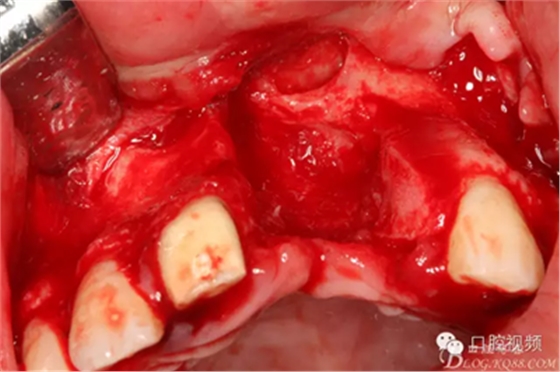

圖12.繼續(xù)清理創(chuàng)面周圍炎性組織

圖13. 清理、沖洗完畢的創(chuàng)面情況